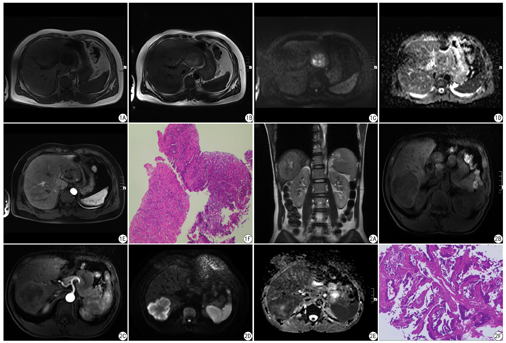

19例不典型肝脓肿的囊性成分T1WI低信号、T2WI高信号,实性成分T1W1等低信号、T2WI稍高信号;CE-MRI:19例不典型肝脓肿,8例为分隔样强化,11例为不规则厚壁强化,其中11例病灶出现肝实质一过性的明显强化;DWI (b值取50 s/mm2)序列,19例不典型肝脓肿囊性成分明显高信号、实性成分高信号;DWI (b值取800 s/mm2)序列,12例不典型肝脓肿囊性成分低信号,实性成分稍高信号;7例不典型肝脓肿囊性成分高信号,实性成分等信号(见图1、图2)。24例肝脏转移瘤的囊性成分T1WI低信号、T2WI高信号,实性成分T1WI等低信号、T2WI稍高信号;CE-MRI:24例肝脏转移瘤中,9例病灶出现环形强化,15例病灶出现不规则厚壁强化,2例病灶出现肝实质一过性的明显强化;DWI (b值取50 s/mm2)24例肝脏转移瘤囊变、坏死区明显高信号,实性成分高信号;DWI (b值取800 s/mm2) 24例肝脏转移瘤囊变、坏死区低信号,实性成分高信号(见图3、4)。CE-MRI诊断不典型肝脓肿13例,准确率为68.42%;CE-MRI联合DWI诊断不典型肝脓肿18例,准确率为94.73%。CE-MRI诊断肝脏转移瘤16例,准确率为66.67%;CE-MRI联合DWI诊断肝脏转移瘤21例,准确率为87.50%。CE-MRI联合DWI诊断不典型肝脓肿、肝脏转移瘤的准确率均高于CE-MRI。